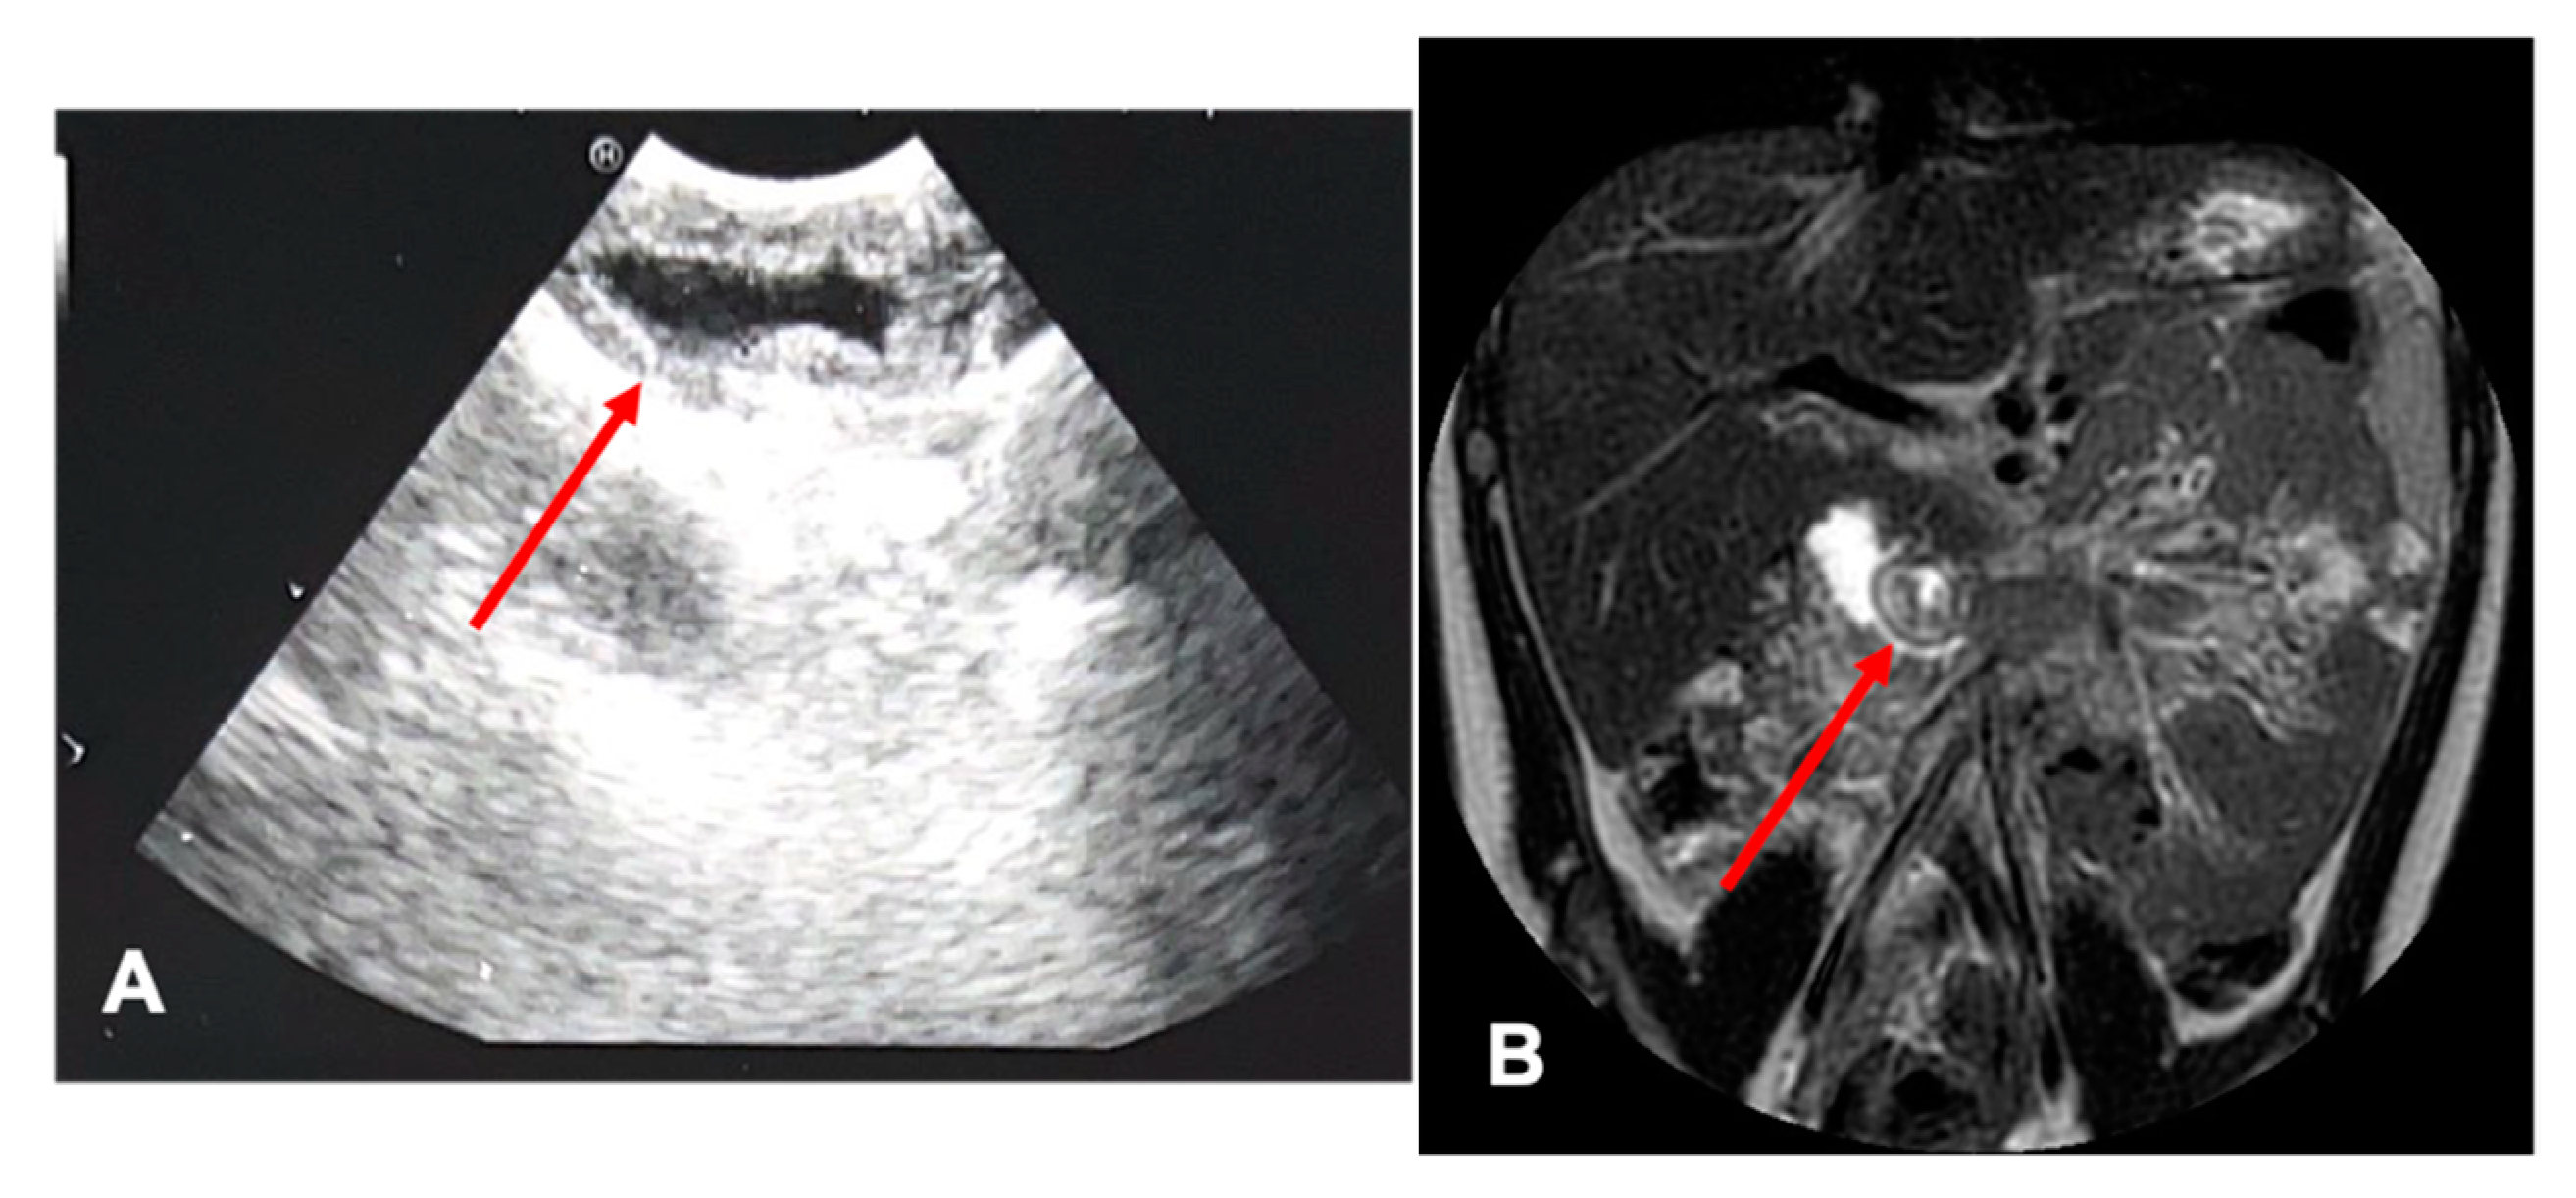

| Radiological investigations | US, MR, CT Scan, VR HMD | US, Cholangio MR | US, X-ray, Cholangio MR, CT, VR HMD | US, Cholangio MR, CT |

| Radiological investigations | US, cholangio-MR, CT Scan | US, cholangio-MRI | US | |